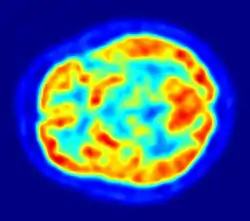

Scintigraphy (from Latin scintilla, "spark"), also known as a gamma scan, is a diagnostic test in nuclear medicine, where radioisotopes attached to drugs that travel to a specific organ or tissue (radiopharmaceuticals) are taken internally and the emitted gamma radiation is captured by gamma cameras, which are external detectors that form two-dimensional images[1] in a process similar to the capture of x-ray images. In contrast, SPECT and positron emission tomography (PET) form 3-dimensional images and are therefore classified as separate techniques from scintigraphy, although they also use gamma cameras to detect internal radiation. Scintigraphy is unlike a diagnostic X-ray where external radiation is passed through the body to form an image.

Another extensive use of scintillography is in medical imaging techniques which use gamma ray detectors called gamma cameras. Detectors coated with materials which scintillate when subjected to gamma rays are scanned with optical photon detectors and scintillation counters. The subjects are injected with special radionuclides which irradiate in the gamma range inside the region of interest, such as the heart or the brain. A special type of gamma camera is the SPECT (Single Photon Emission Computed Tomography). Another medical scintillography technique, the Positron-emission tomography (PET), which uses the scintillations provoked by electron-positron annihilation phenomena.